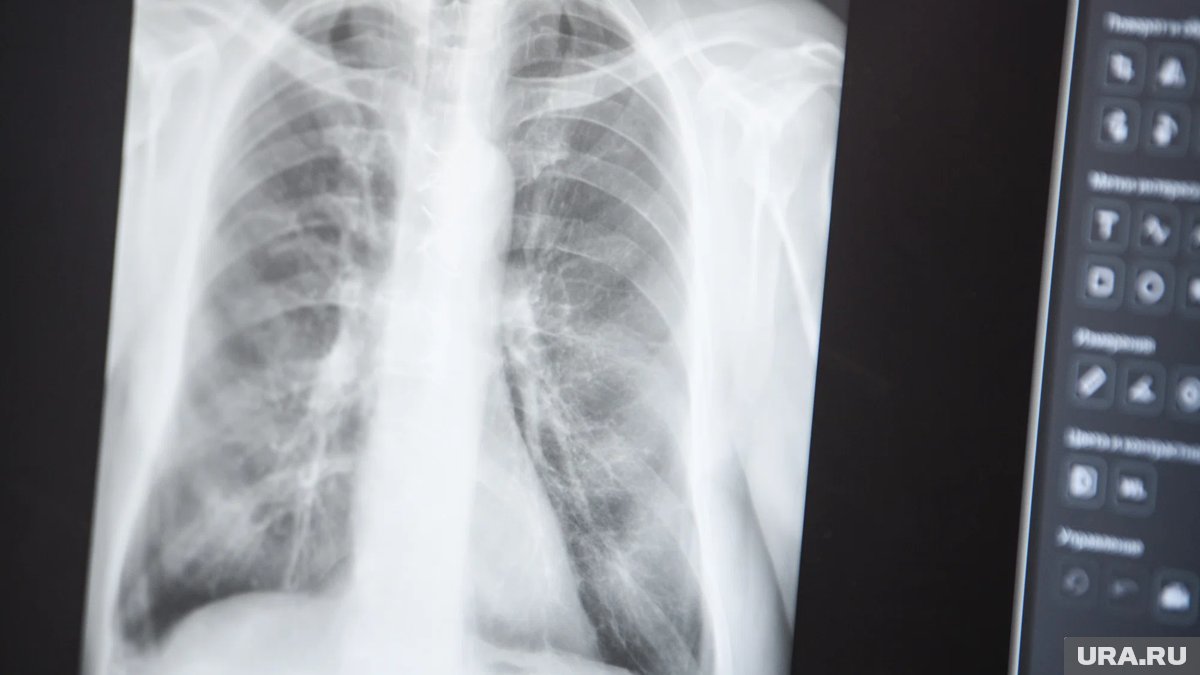

В Свердловской области за последние девять месяцев у жителей обнаружили более 5,8 тысячи разных патологий легких. Их удалось выявить во время профилактических осмотров, рассказали в департаменте информполитики региона.

«В структуре впервые выявленных заболеваний диспансеризация помогла диагностировать 13 случаев туберкулеза. Также обнаружены 198 злокачественных новообразований трахеи, бронхов, легкого, причем 51,5% раковых опухолей медикам удалось выявить на ранних стадиях», — поделилась главный внештатный специалист по медицинской профилактике областного минздрава Дарья Белова.

На данный момент подобные осмотры прошли порядка 1,3 миллиона жителей. Чтобы повысить доступность процедуры, специалисты выезжают на мобильных кабинетах в различные населенные пункты и учреждения.